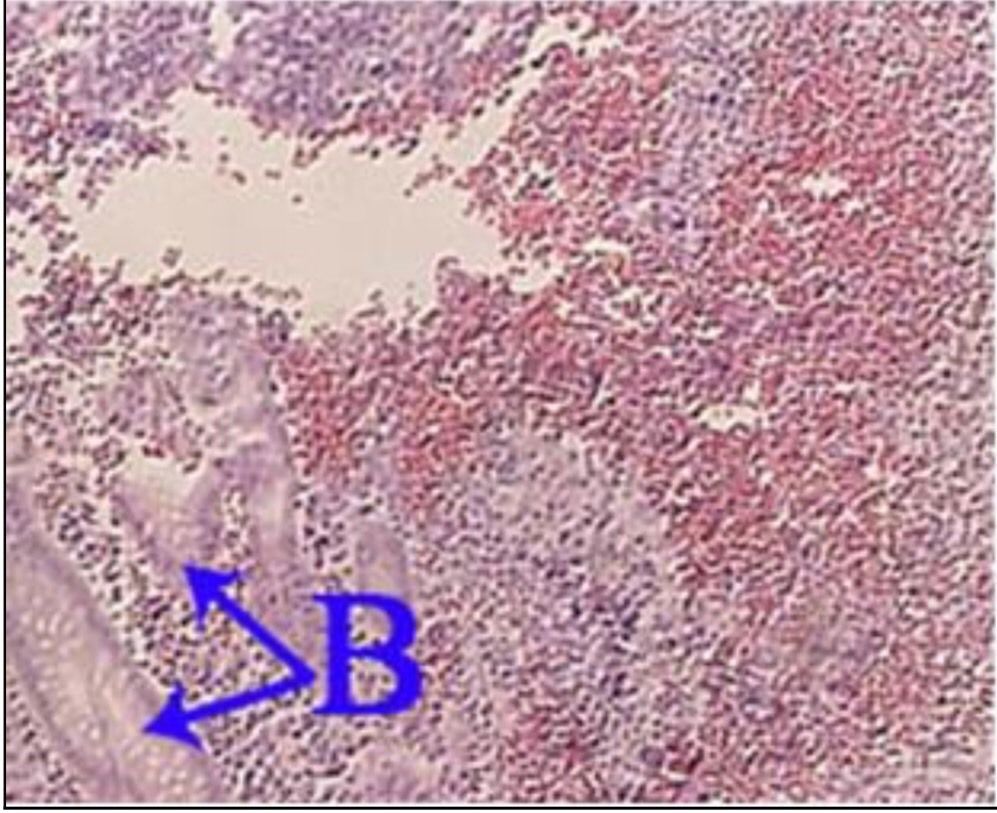

Question 2

Question

What is the correct answer at point B?

Answer

• - épithélium exocervical normal

• - membrane basale

• - cellules anormales

• - épithélium dysplasique sévère

• - massifs carcinomateux